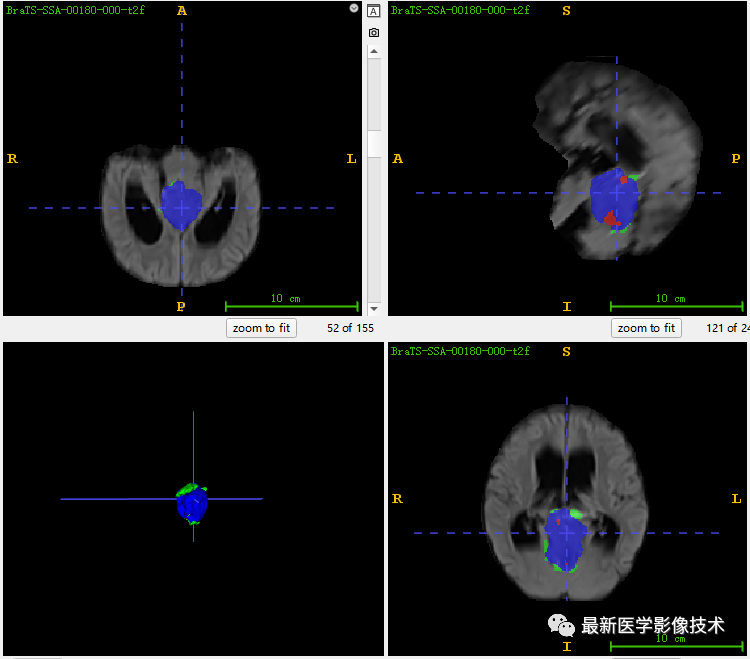

6、验证集分割结果

左图是金标准结果,右图是网络预测结果。

7、测试集分割结果